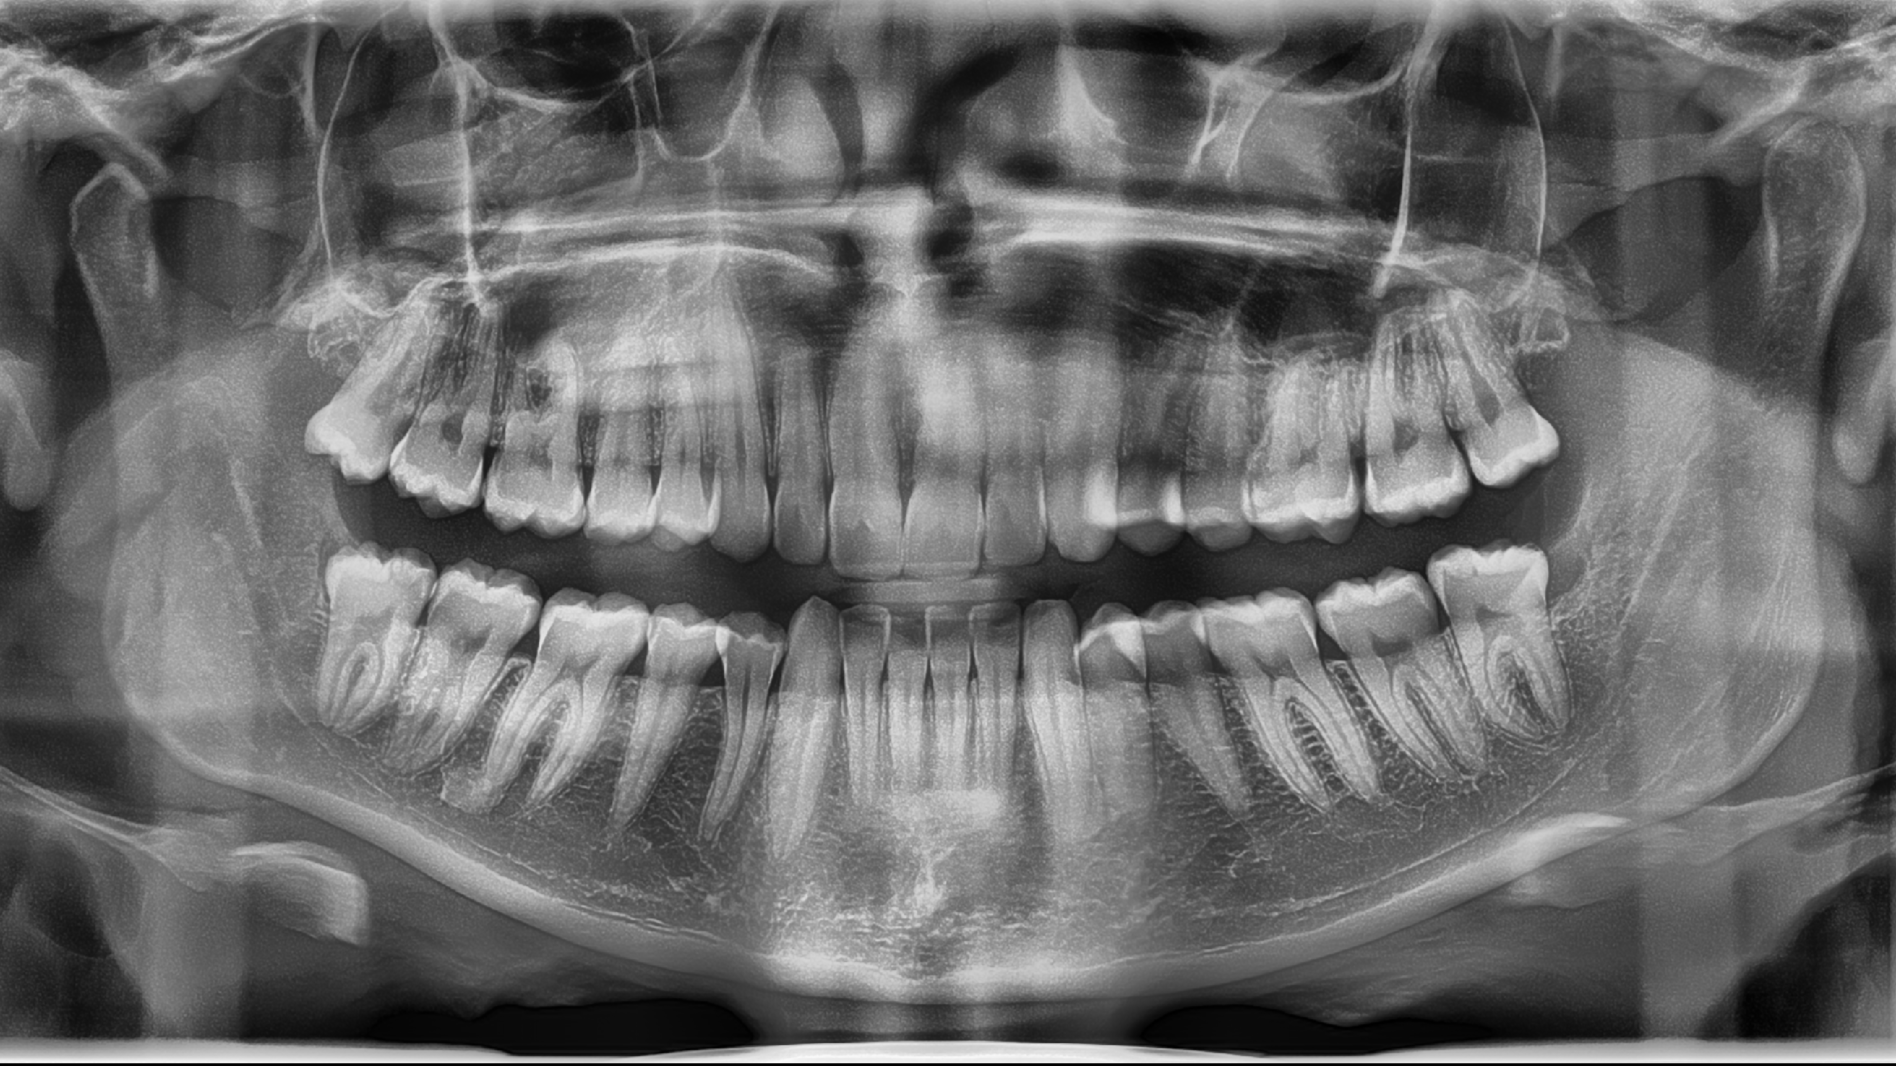

• An OPG (Orthopantomogram) is a wide, panoramic dental X-ray that captures all the teeth, upper and lower jaws, and surrounding bone in a single image. It helps your dentist assess tooth position, wisdom teeth, jaw joints and overall oral health.